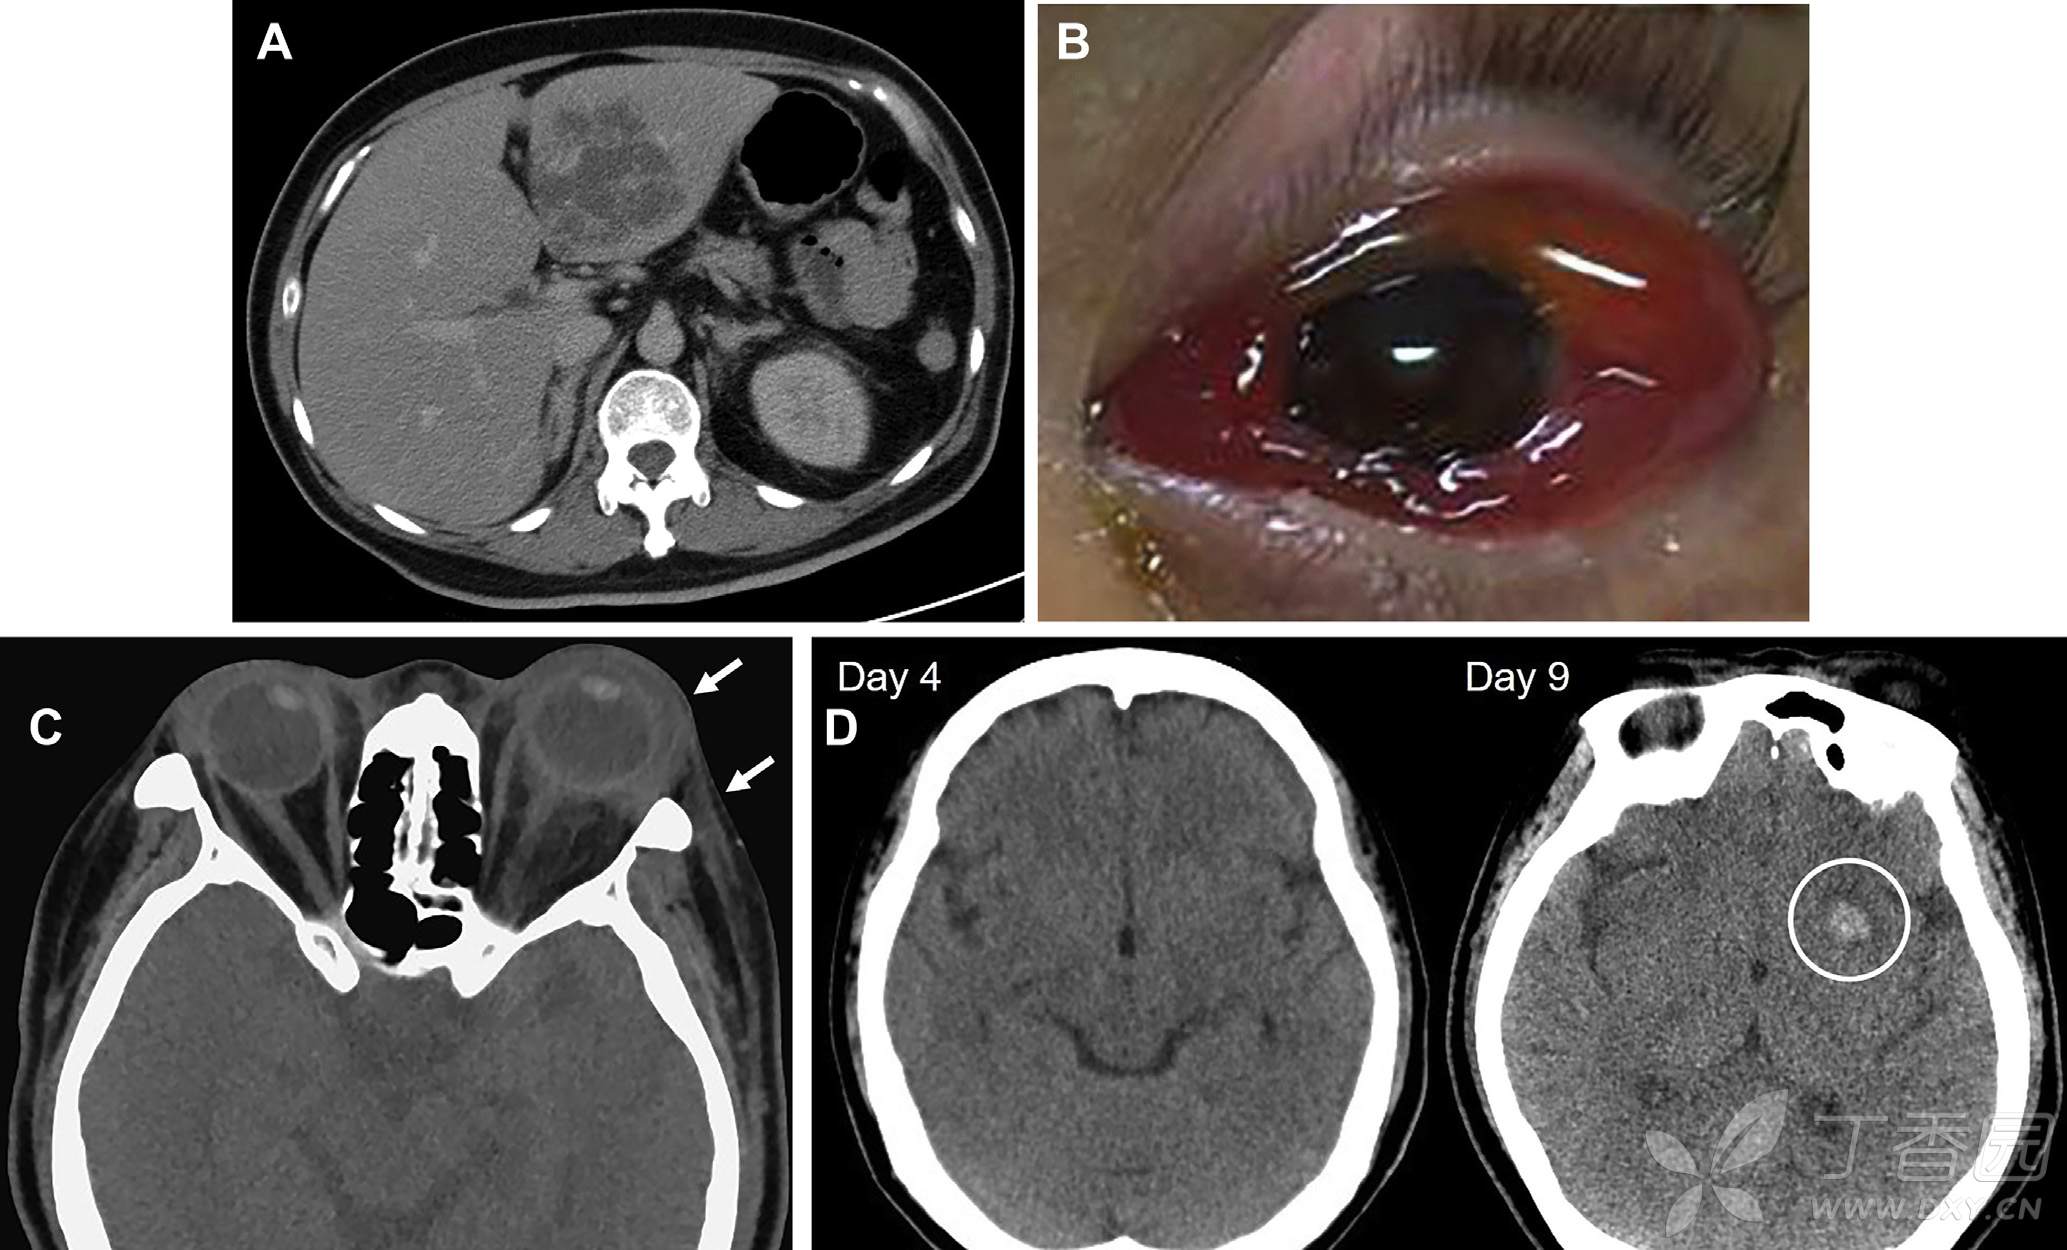

腹部CT扫描提示左肝叶内多分叶状囊性病灶(图A)。

入院后第5天出现左眼突出、眼肌麻痹、结膜水肿(图B),视敏锐度可见“手动”。眼眶CT提示脉络膜巩膜增厚、眶周脂肪带(图C,箭头)。左侧基底节可见1cm大小高密度血肿(图D)。